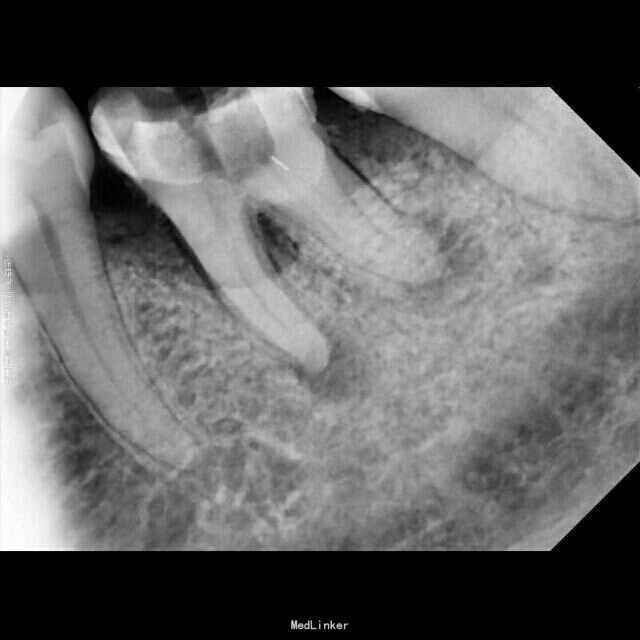

检查:36牙残冠,开髓洞型,叩(+),松(-) 辅查:36牙远中根管口有异物,根尖暗影

诊断:36牙慢性根尖周炎 治疗:36牙探及根管口④,远颊根管口阻塞,选用尖头金刚砂车针去除部分髓底,暴露断针头部,超声(P尖)逆时针振荡,直到断针松动,然后用血管钳取出断针,疏通根管,机扩,充填,术后1个月复查,根尖暗影范围略有缩小